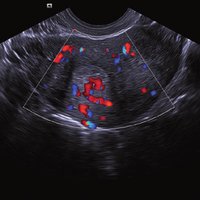

Das ACUSON NX2 Ultraschallsystem besitzt eine zukunftsfähige digitale Plattform mit nahezu unerreichter Bildqualität und sorgt für effiziente und zuverlässige Diagnosedaten. Die Vielseitigkeit des Ultraschallsystems wird mit einem großen kompatiblen Portfolio an Schallköpfen gedeckt, und so ist für jeden Anwendungsbereich etwas dabei. Die Bedienkonsole ist intuitiv aufgebaut und optimiert und erlaubt bis zu vier nach vorne gerichteten Schallkopfanschlüssen für eine enorme Effizienz und schnellen Workflow. So lassen sich bei der fetalen Bildgebung außergewöhnlich detailgetreue Darstellungen des Fetus im Gesicht zeigen oder durch die herausragende Farbdopplersensitivität bei der Darstellung der kleinen Gefäße des zystischen Schilddrüsenknotens kleinste Details erkennen. Weiterhin besticht das NX2 mit einfacher Aufrüstbarkeit bei wachsenden Anforderungen für Ihre zukünftigen Anwendungen und kompatible skalierbare Schallköpfe verringern ihren Kapitaleinsatz um bis zu 31 %.

• Abdomen

• Allgemeinmedizin

• Gefäße

• Gynäkologie/ Geburtshilfe

• Gynäkologie